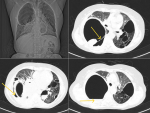

A 52-year-old female patient came to the hospital with complaints of progressive breathlessness and dry cough on and off for 6 months, relieved with medications. High-Resolution Computed Tomography (HRCT) of the thorax showed a large thick-walled cavity showing air-fluid level in the right hemithorax and bilateral pan-acinar, paraseptal emphysematous changes with adjacent consolidation, and ground-glass opacities termed as bullae. A bulla is an air-containing structure bigger than 1 cm in diameter that develops inside the lung parenchyma as a result of disruption, dilation, and convergence of airspaces distal to terminal bronchioles. Massive bullous emphysema, when causing progressive dyspnea, is called "vanishing-lung syndrome." They are avascular radiolucent patches with curvilinear walls less than 1 mm in thickness, so challenging to identify radiologically from pneumothorax. A computed tomography (CT) scan is more sensitive for a precise evaluation, particularly when the bullae are veiled. The clinical image depicts a valuable "double-wall sign" that helps identify pneumothorax from adjacent giant bullae. When air is seen on either side of the bulla wall and parallel to the chest wall, the sign becomes obvious, and the lack of this sign reduces the probability of pneumothorax. A potential pitfall is the false visualisation of a double-wall sign when two bullae are adjacent to one another, sometimes simulating a pneumothorax and causing an apparent double-wall sign. However, a detailed study will show that the pleural gap is airless and the bulla wall is perpendicular to the chest wall. Hence, it is critical to distinguish between bullae and pneumothorax precisely to prevent iatrogenic pneumothorax from needless chest tube insertion.

Figure 1: A) chest X-ray showing large right sided bulla; B) high-resolution computed tomography thorax showing thick wall indicated with arrow; C) sign of double wall (arrow); D) water fluid level indicated with arrow